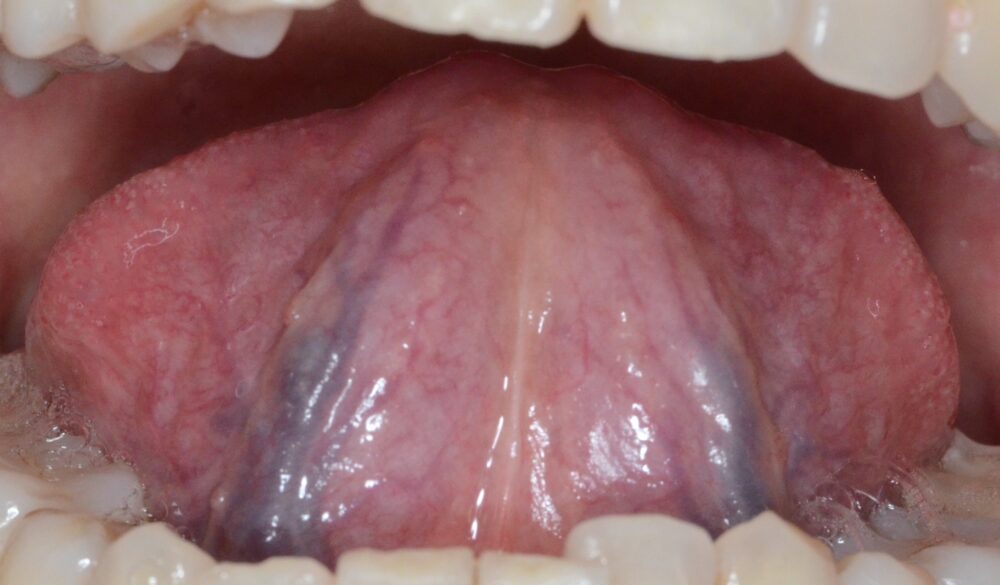

舌は歯の治療後(黒い血管は薄くなっている)

コロナが蔓延してからここ2年間患者さんの舌の状態を診てきましたが、ワクチン接〇者もそうですが「シェディング」の影響を受けた方の多くが「瘀血」という血液循環障害に陥っていました。舌の裏側の血管が黒く浮き出ているので、誰でもすぐ自分が「瘀血」かどうかを知ることが出来ます。

下、瘀血の人の舌(裏に黒い血管が浮き出る)